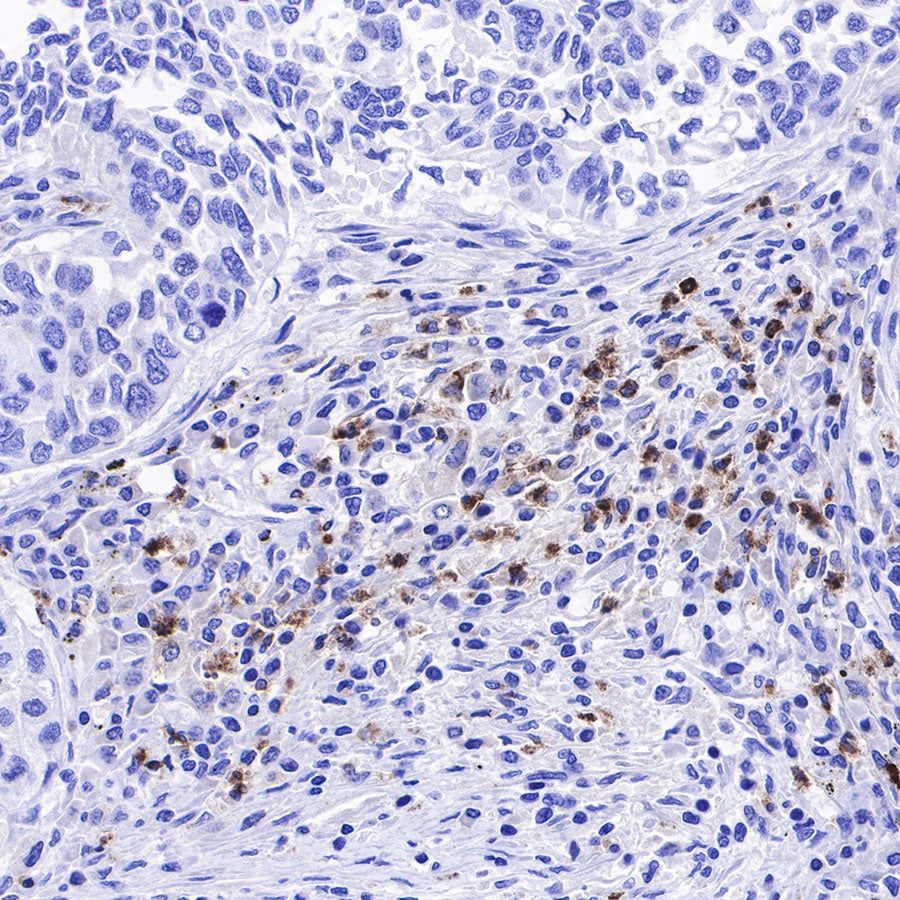

IHC shows positive staining in paraffin-embedded human liver. Anti-Lysozyme antibody was used at 1/100 dilution, followed by a HRP Polymer for Mouse & Rabbit IgG (ready to use). Counterstained with hematoxylin. Heat mediated antigen retrieval with Tris/EDTA buffer pH9.0 was performed before commencing with IHC staining protocol.

IHC shows positive staining in paraffin-embedded human tonsil. Anti-Lysozyme antibody was used at 1/100 dilution, followed by a HRP Polymer for Mouse & Rabbit IgG (ready to use). Counterstained with hematoxylin. Heat mediated antigen retrieval with Tris/EDTA buffer pH9.0 was performed before commencing with IHC staining protocol.

IHC shows positive staining in paraffin-embedded human spleen. Anti-Lysozyme antibody was used at 1/100 dilution, followed by a HRP Polymer for Mouse & Rabbit IgG (ready to use). Counterstained with hematoxylin. Heat mediated antigen retrieval with Tris/EDTA buffer pH9.0 was performed before commencing with IHC staining protocol.

IHC shows positive staining in paraffin-embedded human colon cancer. Anti-Lysozyme antibody was used at 1/100 dilution, followed by a HRP Polymer for Mouse & Rabbit IgG (ready to use). Counterstained with hematoxylin. Heat mediated antigen retrieval with Tris/EDTA buffer pH9.0 was performed before commencing with IHC staining protocol.

IHC shows positive staining in paraffin-embedded human ovarian cancer. Anti-Lysozyme antibody was used at 1/100 dilution, followed by a HRP Polymer for Mouse & Rabbit IgG (ready to use). Counterstained with hematoxylin. Heat mediated antigen retrieval with Tris/EDTA buffer pH9.0 was performed before commencing with IHC staining protocol.

IHC shows positive staining in paraffin-embedded human lung squamous cell carcinoma. Anti-Lysozyme antibody was used at 1/100 dilution, followed by a HRP Polymer for Mouse & Rabbit IgG (ready to use). Counterstained with hematoxylin. Heat mediated antigen retrieval with Tris/EDTA buffer pH9.0 was performed before commencing with IHC staining protocol.

IHC shows positive staining in paraffin-embedded human endometrial carcinoma. Anti-Lysozyme antibody was used at 1/100 dilution, followed by a HRP Polymer for Mouse & Rabbit IgG (ready to use). Counterstained with hematoxylin. Heat mediated antigen retrieval with Tris/EDTA buffer pH9.0 was performed before commencing with IHC staining protocol.